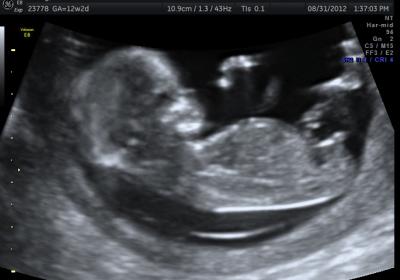

Why are boy nubs all so different from each other?

Hey ladies! Just pondering nubs until my anatomy scan. After seeing so many nubs on the internet, I'm wondering, why do boy nubs differ so much? Girls tend to be all similar: close to the bottom, straight out, some with a fork.

But boys: some are little stacked blobs, some are long straight lines with a bump at the end, some look like hockey sticks or pipes, some stick straight up and some are pretty close to parallel. What the heck? I thought girls were supposed to have the complicated anatomy! Haha.

But here are some examples of what I mean with the different "types":